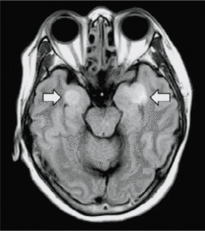

Encefalite sviluppata da una paziente Covid19

Una tempesta in tutto il corpo

17 maggio 2020 - Un articolo pubblicato sulla rivista Science fa delle interessanti considerazioni sul danno che Covid-19 può causare a molti organi tra cui cuore e vasi sanguigni, reni, intestino e cervello. Sebbene i polmoni rappresentino il “ground zero” della malattia, il danno causato dal virus può estendersi a molti organi e la comprensione di questa diffusione, potrebbe aiutare i medici a curare le persone infette che si ammalano in maniera particolarmente grave. L’articolo si chiede: una tendenza pericolosa e recentemente osservata alla coagulazione del sangue, trasforma alcuni casi lievi in emergenze potenzialmente letali? Una risposta immunitaria troppo sollecita è alla base dei casi peggiori, suggerendo che il trattamento con farmaci immunosoppressori potrebbe aiutare? Cosa spiega l'ossigeno nel sangue sorprendentemente basso che alcuni medici segnalano in pazienti che non hanno ancora problemi respiratori? Adottare un approccio sistemico può essere utile quando si inizia a pensare alle terapie. Nonostante i numerosi articoli che si riversano su riviste e server, un'immagine chiara è ancora sfuggente, poiché il virus si comporta come nessun patogeno che l'umanità abbia mai visto.